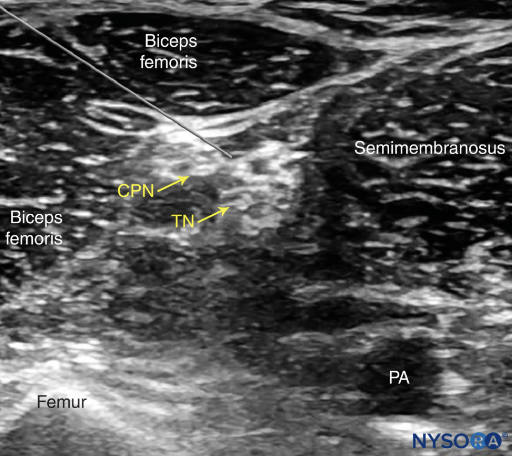

• The sciatic nerve consists of two separate nerve trunks: the tibial and common peroneal nerves. A common paraneural sheath envelops these two nerves from their origin in the pelvis.

• As the sciatic nerve descends toward the knee, the two components eventually diverge just proximal to the popliteal fossa, giving rise to the tibial nerve (TN) and common peroneal nerve (CPN).

• This division of the sciatic nerve usually occurs between 50 and 120 mm proximal to the popliteal fossa crease.

• It is recommended to perform the nerve block at the level where TN and CPN start diverging but are still in the common sciatic nerve sheath.

• The sciatic nerve at the split into the CPN and TN is seen just above and slightly to the right of the popliteal vessels